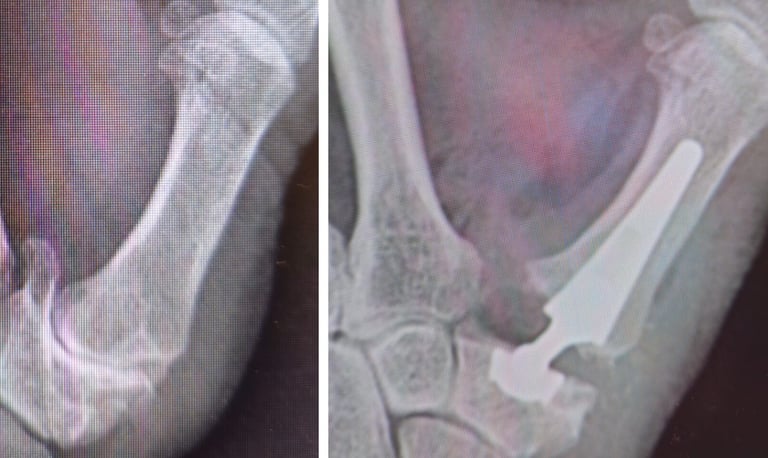

Fracturas y secuelas

Artrosis de muñeca

Artrosis